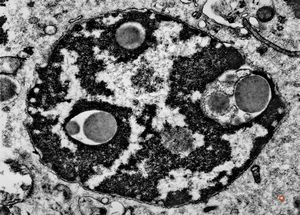

F,52y. | intranuclear inclusions - plasmocytoma